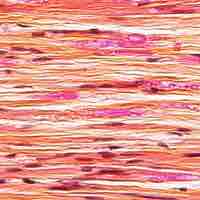

Bones adapt to the muscle force loads placed on them, becoming thicker and stronger under stress/use and weaker and thinner when unused.